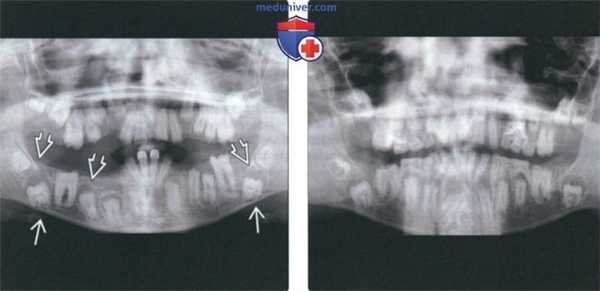

(Слева) На кадрированной панорамной рентгенограмме у мальчика определяются признаки гипопластического варианта несовершенного амелогенеза. Визуализируются множественные непрорезавшиеся зубы и патологически измененные корни. Кроме того, определяется легкое увеличение нескольких зубных фолликулов.

(Справа) На кадрированной панорамной рентгенограмме определяются признаки гипопластического варианта несовершенного амелогенеза у сестры предыдущего пациента. Аналогично поражены временные и постоянные зубы.